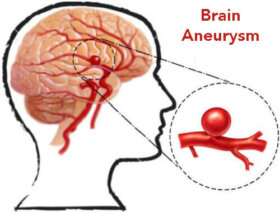

동맥류는 동맥 혈관 벽의 약화로 인한 동맥의 이상 비대증이라고 할 수 있다. 이처럼 심각한 질환은 대개 50세 이상의 여성들에게 영향을 미친다. 이 글에서는 동맥류의 진단 및 예방법을 소개한다.